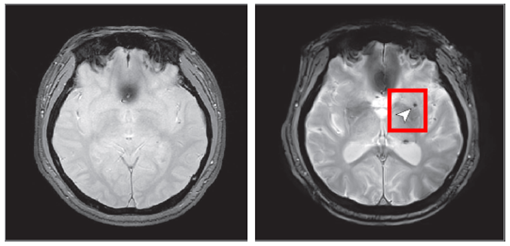

< 8년 후 뇌 미세출혈이 발생한 뇌영상 이미지 >

노화 기반 참여                     8년 후 추적조사 참여

뇌 미세출혈은 뇌 속의 작은 혈관이 손상되어 출혈이 발생하는 것으로, 뇌졸중(특히 뇌출혈) 등 심각한 뇌혈관 질환의 주요 위험요인으로 알려져 있다.

연구 결과, 중등도 이상의 폐쇄성 수면무호흡증을 가진 사람은 수면무호흡증이 없는 사람에 비해 뇌 미세출혈이 발생할 위험이 약 2배 증가하는 것으로 나타났다. 반면, 경증 수면무호흡증에서는 위험 증가가 관찰되지 않았다.